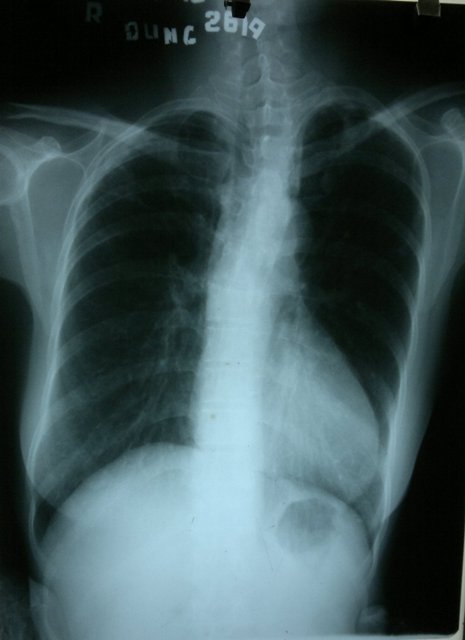

Thất phải lớn trong Fallot 4